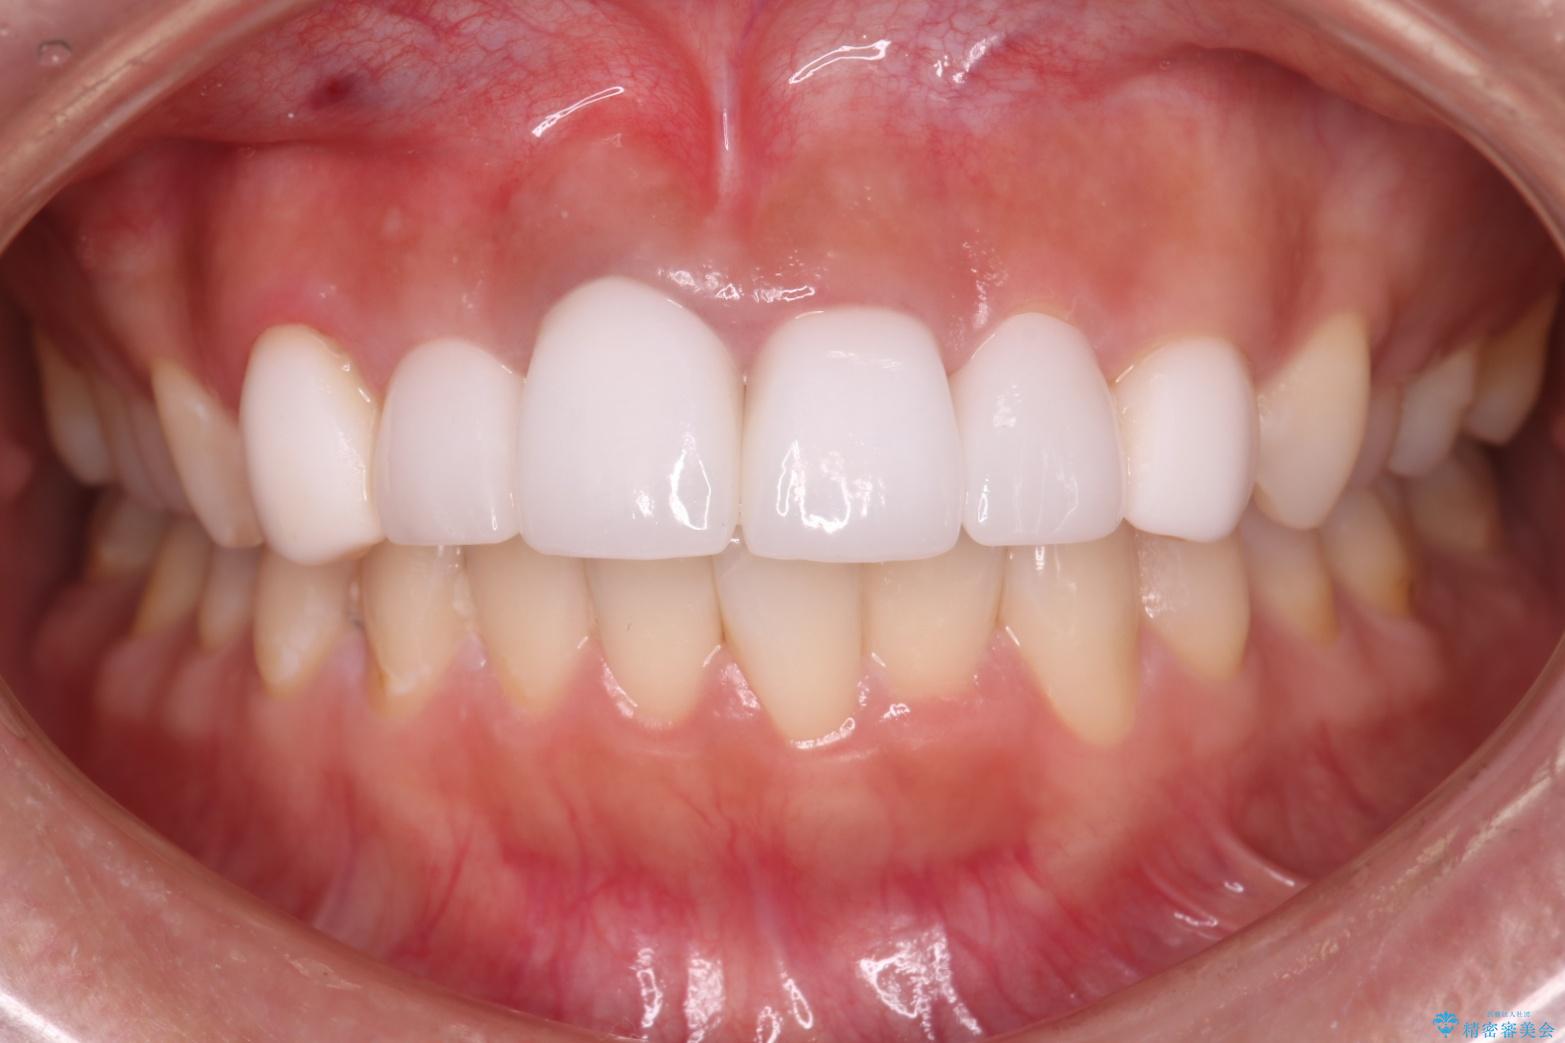

- 他院で治療した前歯の色が気になるということで来院された患者様です。前歯に色の差があり、レントゲンから内部にう蝕も見られたため、審美性に優れ、う蝕になりにくいオールセラミッククラウンで治療いたしました。

清掃性も上がったおかげで、歯肉の状態も良好に保てています。

色の調和もとれたので非常に満足いただけました。